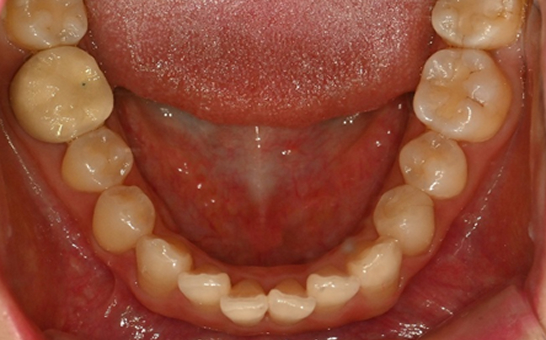

※ 바른선택치과의원은 의료법을 준수하며 위 케이스는 실제 내원 환자분의 동의하에 공개된 사진과 동일한 환자분께 같은 조건에서 촬영한 사진을 활용했습니다.

개인에 따라 진료 및 치료 방법이 다르게 적용할 수 있으며, 효과와 부작용이 개인마다 다르게 나타날 수 있는 점을 안내해 드리며, 진료 전 전문의료진과 충분한 상담을 권해드립니다.